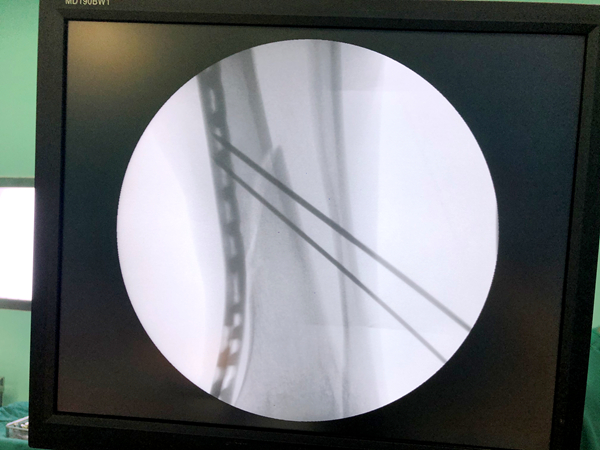

近日,我院骨科接连为数名患者实施了胫骨中下段粉碎骨折MIPPO微创手术。手术的成功开展,标志着我院治疗胫骨粉碎性骨折进入真正的“微创时代”。

随着社会的进步与发展,人们对外伤骨折的治疗要求越来越高,医院骨科结合大量临床经验,积极探索引进了微创经皮钢板内固定(MIPPO)技术。运用“内支架”概念进行骨折固定,用钢板对骨折行桥接固定,利用肌腱复位作用及间接复位技术进行骨折复位,具有创伤小,术后恢复快等优点。

骨关节科主任杨阳介绍,骨折治疗的目的是尽早使肢体功能恢复到受伤前的水平以及减少并发症的发生。与传统开放式骨折治疗方法相比,MIPPO技术远离骨折部位进行复位,为骨折愈合、软组织修复提供良好的生物学环境,能最大程度地保护骨折处血供,促进骨折愈合,减少感染和再骨折的危险性,维持骨折稳定性。MIPPO技术的成功应用,充分证明了市中西医结合医院骨科人攻坚克难的能力与决心,我们将不断探求微创新技术,更好地造福百姓。